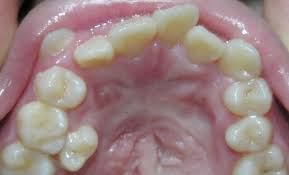

4. Răng mọc lệch: Phổ biến nhất là răng nanh hàm trên và răng khôn. Trong trường hợp răng khôn mọc lệch thì nhổ răng là cách duy nhất để ngăn chặn những tình huống xấu hơn có thể xảy ra.

Răng sâu    Răng nha chu trầm trọng   Răng bị nhiễm trùng

Răng mọc lệch   Răng chỉnh hình             Răng bị chấn thương